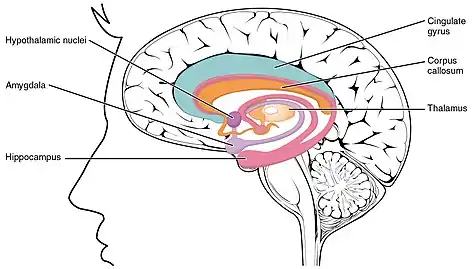

The pituitary gland (or hypophysis cerebri) is an endocrine gland in vertebrates. In humans, the pituitary gland is located at the base of the brain, protruding off the bottom of the hypothalamus. The human pituitary gland is oval shaped, about the size of a chickpea,[2] and weighs 0.5 grams (0.018 oz) on average.

Structure

In humans, the pituitary gland rests upon the hypophyseal fossa of the sphenoid bone, in the center of the middle cranial fossa. It sits in a protective bony enclosure called the sella turcica, covered by the dural fold diaphragma sellae.[3]

Location of the pituitary gland in the human brain

Location of the pituitary gland in the human brain Pituitary and pineal glands